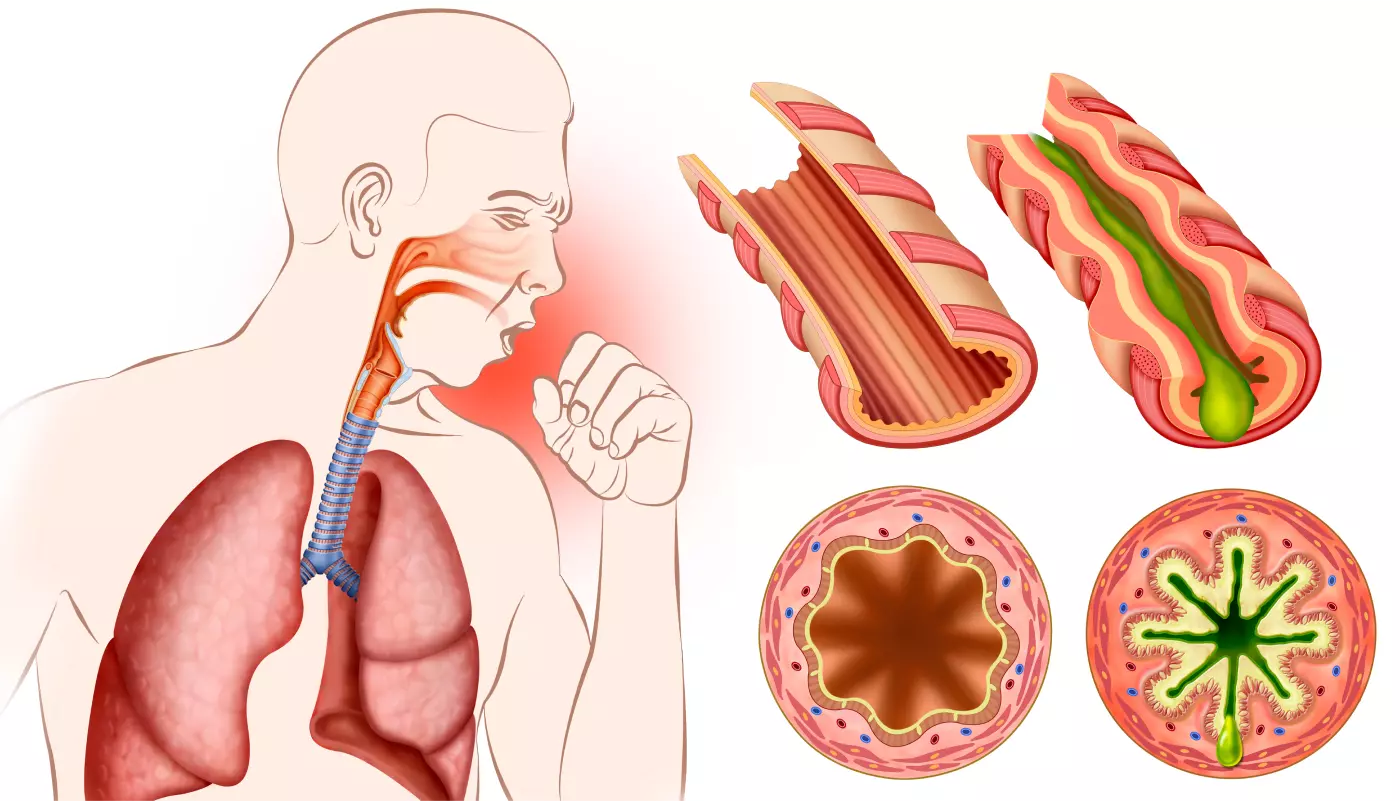

More than a billion people worldwide struggle with breathing problems linked to mucus, and it's not something to take lightly. Mucus buildup can lead to reduced airflow and shortness of breath. This can be uncomfortable, sometimes painful, and in thankfully rare cases, even fatal.

As a bonus, the vibrations caused by OPEP dislodge the thick mucus caused by certain respiratory conditions. After OPEP, you can expel the mucus by coughing, reducing the tight grip it exerts on your airways.

Before and after RespiraFix

Even better, as your airways open up, you’ll be able to take deeper, more satisfying breaths. This not only delivers more precious oxygen to your bloodstream but also increases your lung capacity over time. It’s a “virtuous circle” that will help you feel healthier and breathe better.